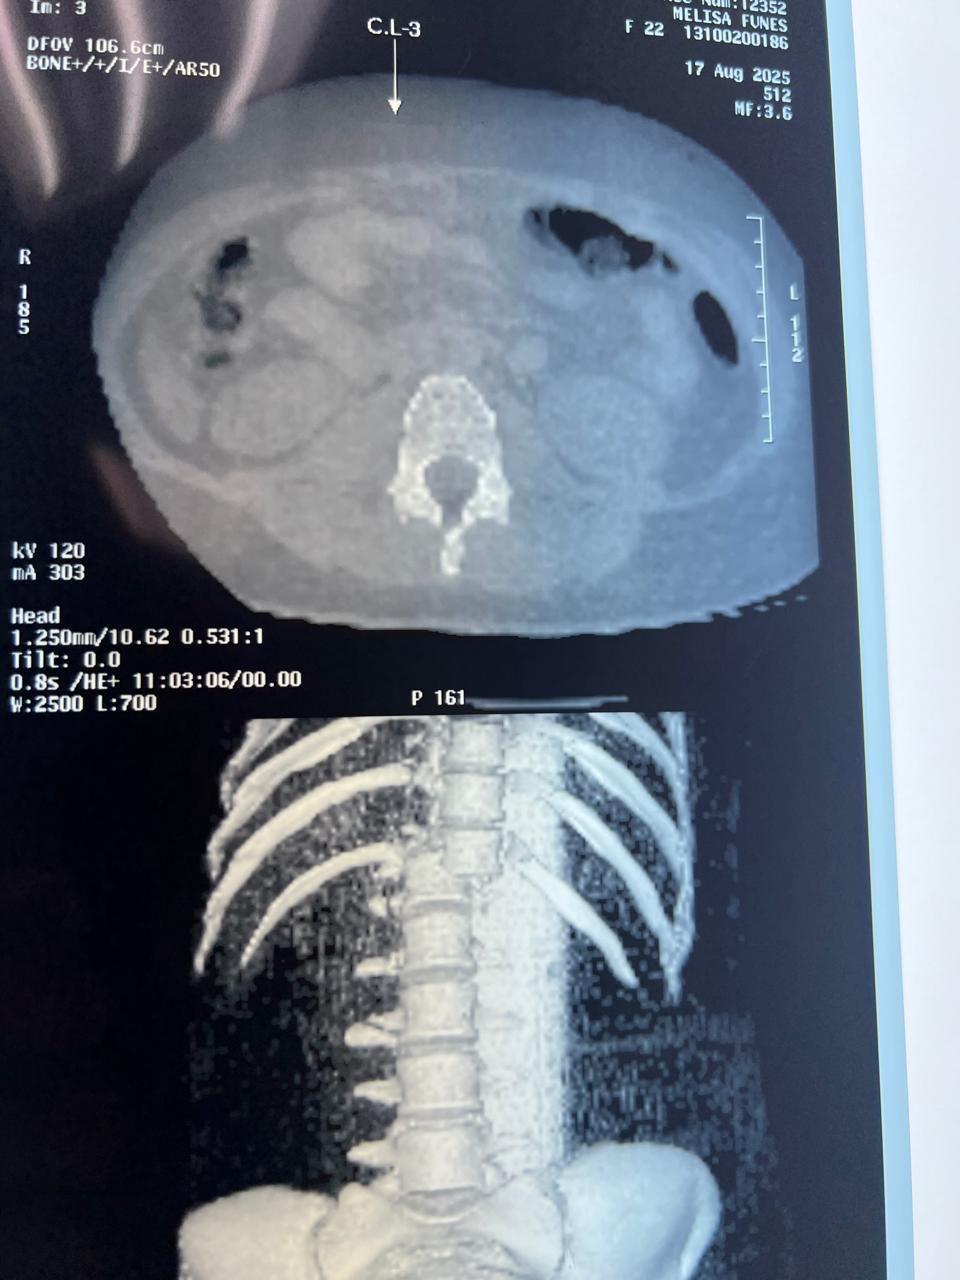

El caso de Nelsy Melissa Fúnez López, una madre de 22 años, ha provocado el repudio de las redes sociales. Ella se encuentra interna con un disgnóstico grave en el hospital Mario Catarino Rivas tras caerse de la popular rueda de Chicago en unas atracciones que se encuentran en Santa Rosa de Copán.

Fúnez López urge de medio millón de lempiras para realizarse varias operaciones, entre ellas una de columna.